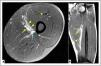

Case 1. Distal myofascial injury 2A (BAMIC) in the VM. A Axial T2 Fat-sat section. B Coronal T2 Fat-sat section. Arrowheads (Interstitial edema in the VM), Arrow (hematoma Hunter's canal). MRI evidence of myofascial damage surrounding the deep area of the VM. Exist also a minimal hematoma located posterior to the sartorius muscle, it was a challenge for the clinical evolution: It initially compressed the Hunter's canal and increased the sensitivity of the area, subsequently produced a hypertrophic laminar scar and reinjury after one month.